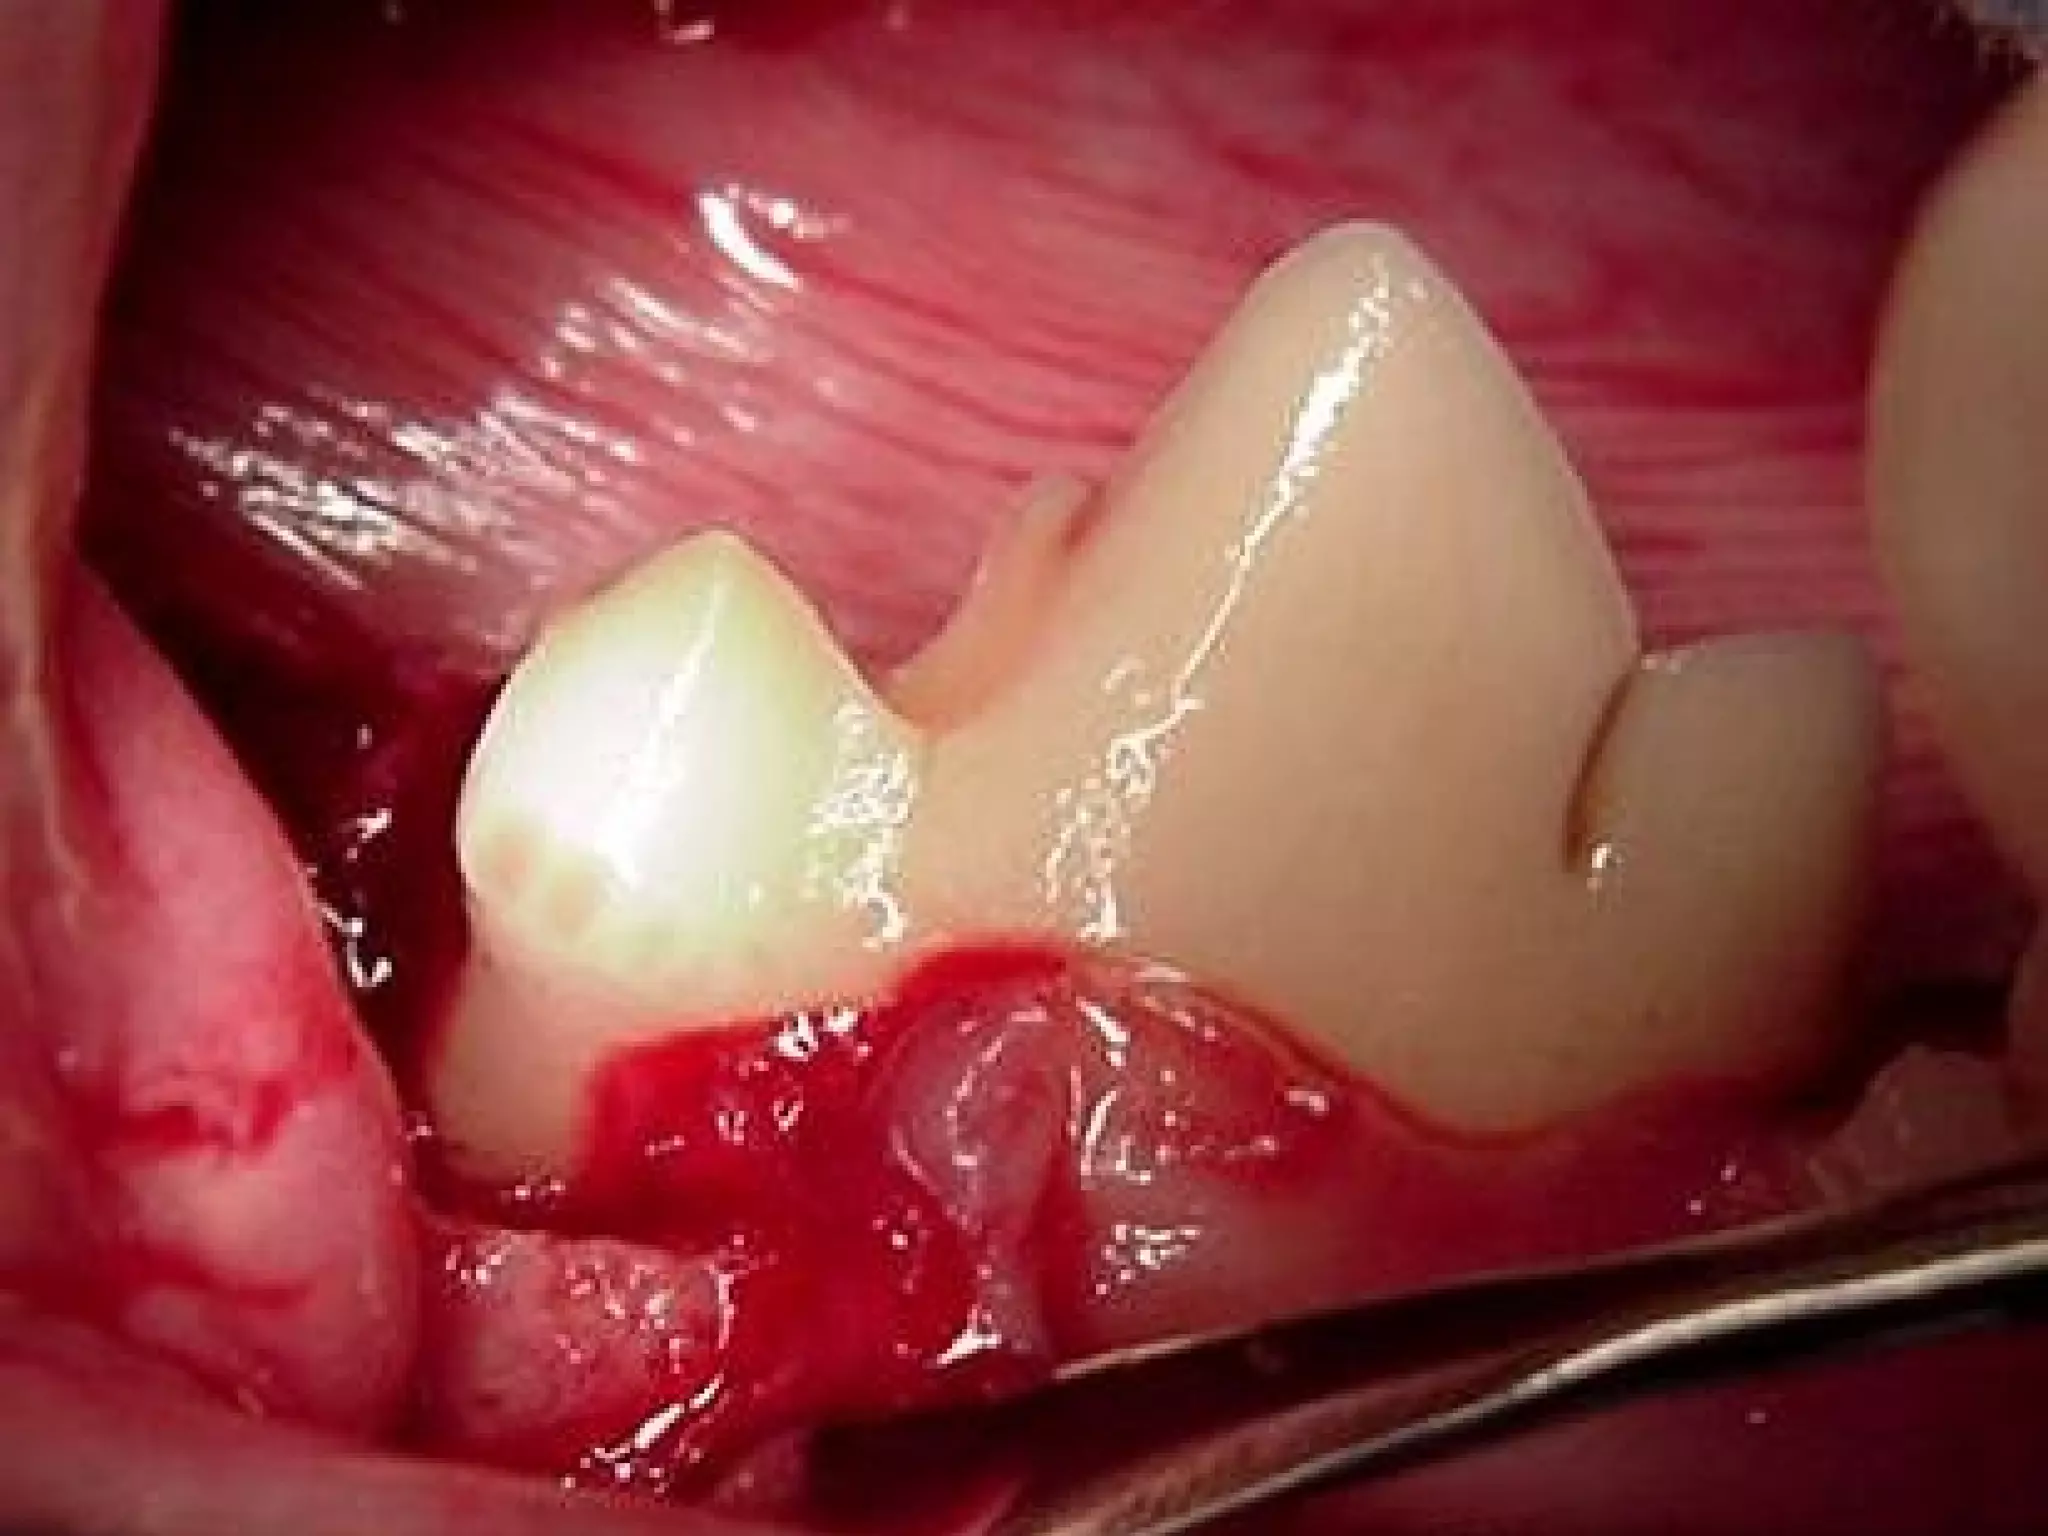

What is the disease present here?

Anatomical description of the

affected tooth?

• 38.

What is thedisease present here? Anatomical description of the affected tooth? 38